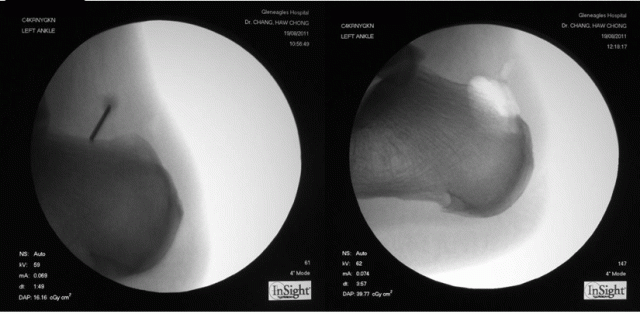

I use the fluoroscope (x-rays) to localise the position of the Haglund’s exostosis.

An intra-operative fluroscopy (x-rays) is taken to confirm complete removal of the Haglund’s protruberance.